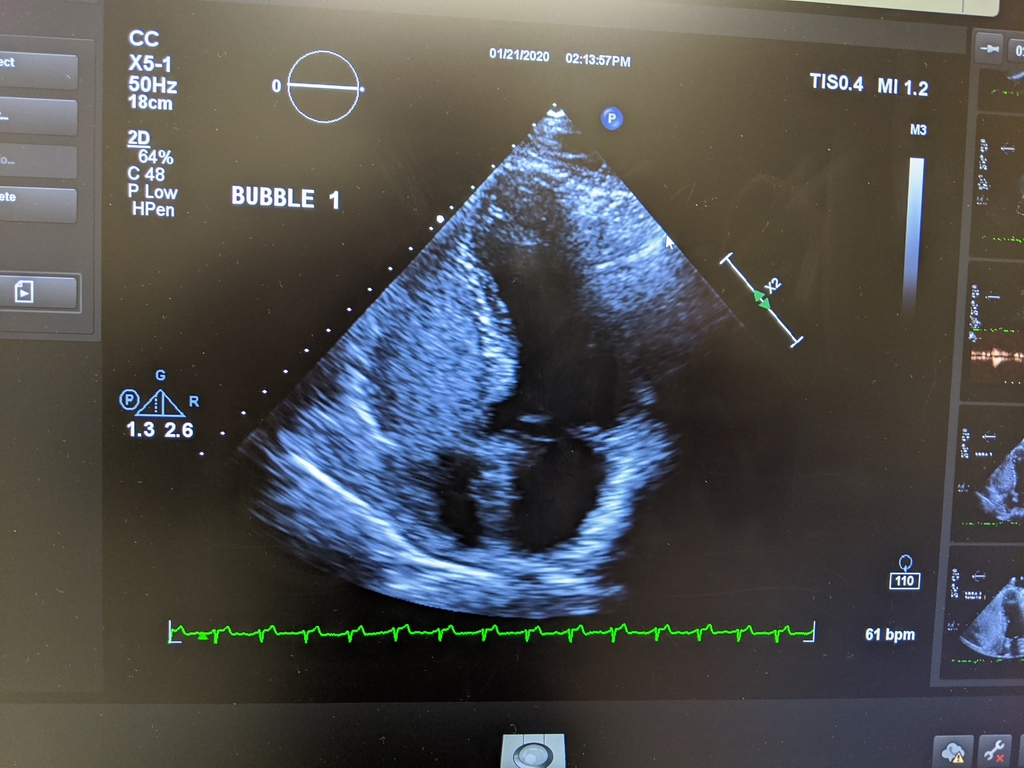

During an echocardiogram session, they added a bubble test to look for any leakage between the two sides of my heart. This is a playback with an upside-down image showing bubbles on the left (my right ventricle).

0121A_EchocardioBubbleTest.jpg (529 Kb) (under photos/20/Random/)